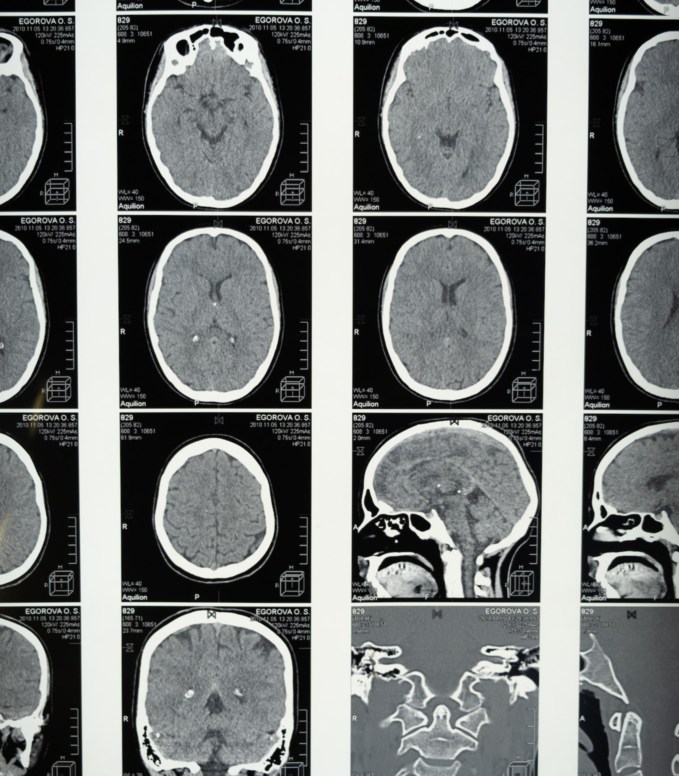

Moreover, the significance of accurate MRI reports becomes profoundly pronounced in avoiding unnecessary medical tests and procedures. In critical medical conditions, swift and precise diagnosis can be the difference between life and death.

When MRI results are verifiable and error-free, medical professionals can make prompt and well-informed decisions, removing redundant tests and procedures that might exacerbate a patient’s condition. This optimizes healthcare efficiency and resource allocation and minimizes the physical and emotional strain on patients, who can rest assured that their treatment plans are optimized for their specific needs.